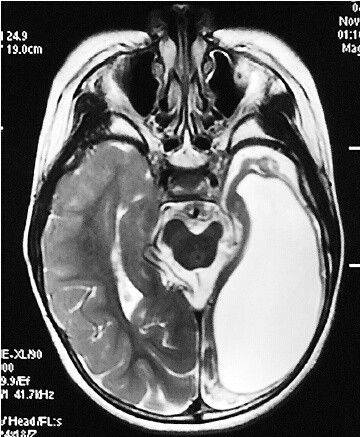

人类的大脑分为左右两个半球。随着医学技术的发展,在某些特殊情况下,我们能够通过切除患者左半脑的方式来治疗癫痫。这就是说,即便只保留左右半脑中的一个,患者也有几率存活下来。

半脑人的脑部扫描